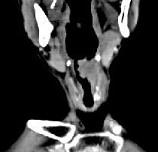

问题 男,53岁,咽部不适半年余,近两个月感咽部疼痛,声嘶,CT如图所示,应诊断为()

选项 A.乳头状瘤 B.喉癌 C.梨状窝癌 D.喉肉芽肿 E.喉部纤维瘤

答案 B